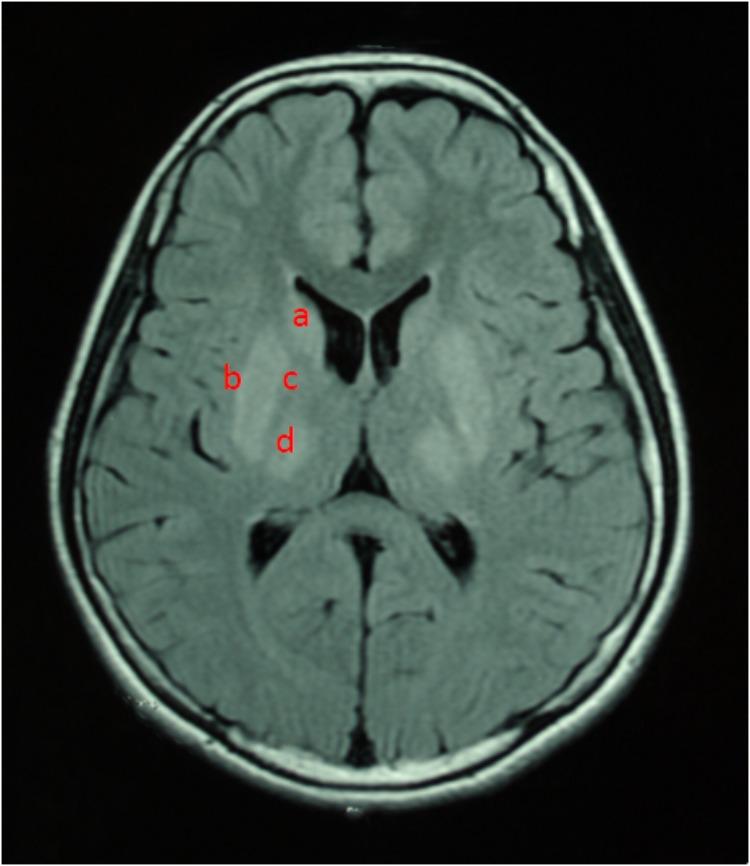

Wilson's disease (WD) is an inborn copper metabolism disease. Sex differences in clinical features of WD patients have been reported; however, the effect of sex on brain MRI is still unclear, especially for Chinese WD patients. Therefore, we aimed to examine sex differences in clinical correlates and brain MRI changes in WD patients in a Chinese Han population. 535 WD patients were enrolled and underwent MRI scanning. These patients were subdivided by the clinical symptoms, Kayser-Fleischer (K-F) rings, laboratory tests and sex. The mean age of onset and diagnosis, disease latency, localization of brain MRI lesions, and the level of copper metabolism were compared between male and female patients. The neuropsychiatric form (452 and 84.5%) was the most common subtype. Compared to female patients, male patients had a higher percentage in three clinical forms: neuropsychiatric form (263 and 58.2%), hepatic form (41 and 59.4%), and presymptomatic form (10 and 71.4%). In the neuropsychiatric form, male patients had the earlier age of onset and definitive diagnosis, and shorter time of disease latency than female patients. Putamen was the most common site for lesions in brain MRI of three groups. In the hepatic form, more male patients showed the ventricular widening than female patients (14/41 vs. 3/28; < 0.05). The level of serum ceruloplasmin and copper of WD patients with neuropsychiatric form was higher than that of male patients with hepatic or presymptomatic form. In women, however, patients of presymptomatic form have the highest level of the ceruloplasmin, and the level of serum copper in hepatic patients was highest. Our findings suggest sex differences in the percentage of three clinical forms. Meanwhile, the mean age of onset and diagnosis of female was higher than male, also happened in the disease latency. Only in the hepatic form, there was a sex difference in the ventricular widening.

威尔逊病(WD)是一种先天性铜代谢疾病。已有报道称WD患者的临床特征存在性别差异;然而,性别对脑部MRI的影响仍不明确,尤其是对于中国WD患者。因此,我们旨在研究中国汉族WD患者临床相关性和脑部MRI变化的性别差异。招募了535例WD患者并进行了MRI扫描。这些患者根据临床症状、凯泽-弗莱舍尔(K-F)环、实验室检查和性别进行了细分。比较了男性和女性患者的平均发病年龄和诊断年龄、疾病潜伏期、脑部MRI病变的定位以及铜代谢水平。神经精神型(452例,占84.5%)是最常见的亚型。与女性患者相比,男性患者在三种临床类型中的比例更高:神经精神型(263例,占58.2%)、肝型(41例,占59.4%)和症状前型(10例,占71.4%)。在神经精神型中,男性患者的发病年龄和确诊年龄更早,疾病潜伏期比女性患者短。壳核是三组脑部MRI中最常见的病变部位。在肝型中,男性患者出现脑室增宽的比例高于女性患者(14/41比3/28;<0.05)。神经精神型WD患者的血清铜蓝蛋白和铜水平高于肝型或症状前型男性患者。然而,在女性中,症状前型患者的铜蓝蛋白水平最高,肝型患者的血清铜水平最高。我们的研究结果表明三种临床类型的比例存在性别差异。同时,女性的平均发病年龄和诊断年龄高于男性,疾病潜伏期也是如此。仅在肝型中,脑室增宽存在性别差异。